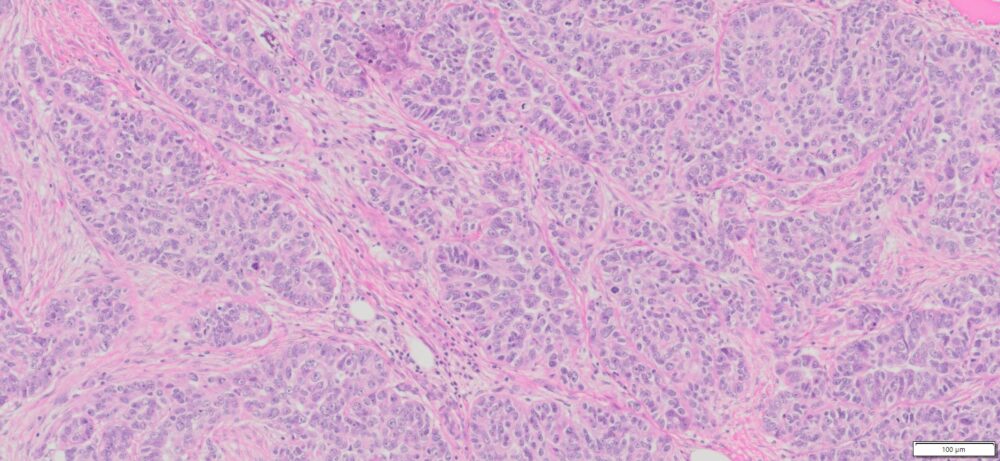

Description

| Organ& Tissue | Pathology Diagnosis | Gender/Age | % Tumor Area | Grade | TMN Stage | IHC Biomarkers |

| Human Ovary | High Grade Serous Carcinoma (HGSC) FFPE Sections | Female/67 | 80% | III | NA | ER(+),Pax-8 (+),WT-1(+),p16(+),p53(+),Ck7 (+), CK20(-) |